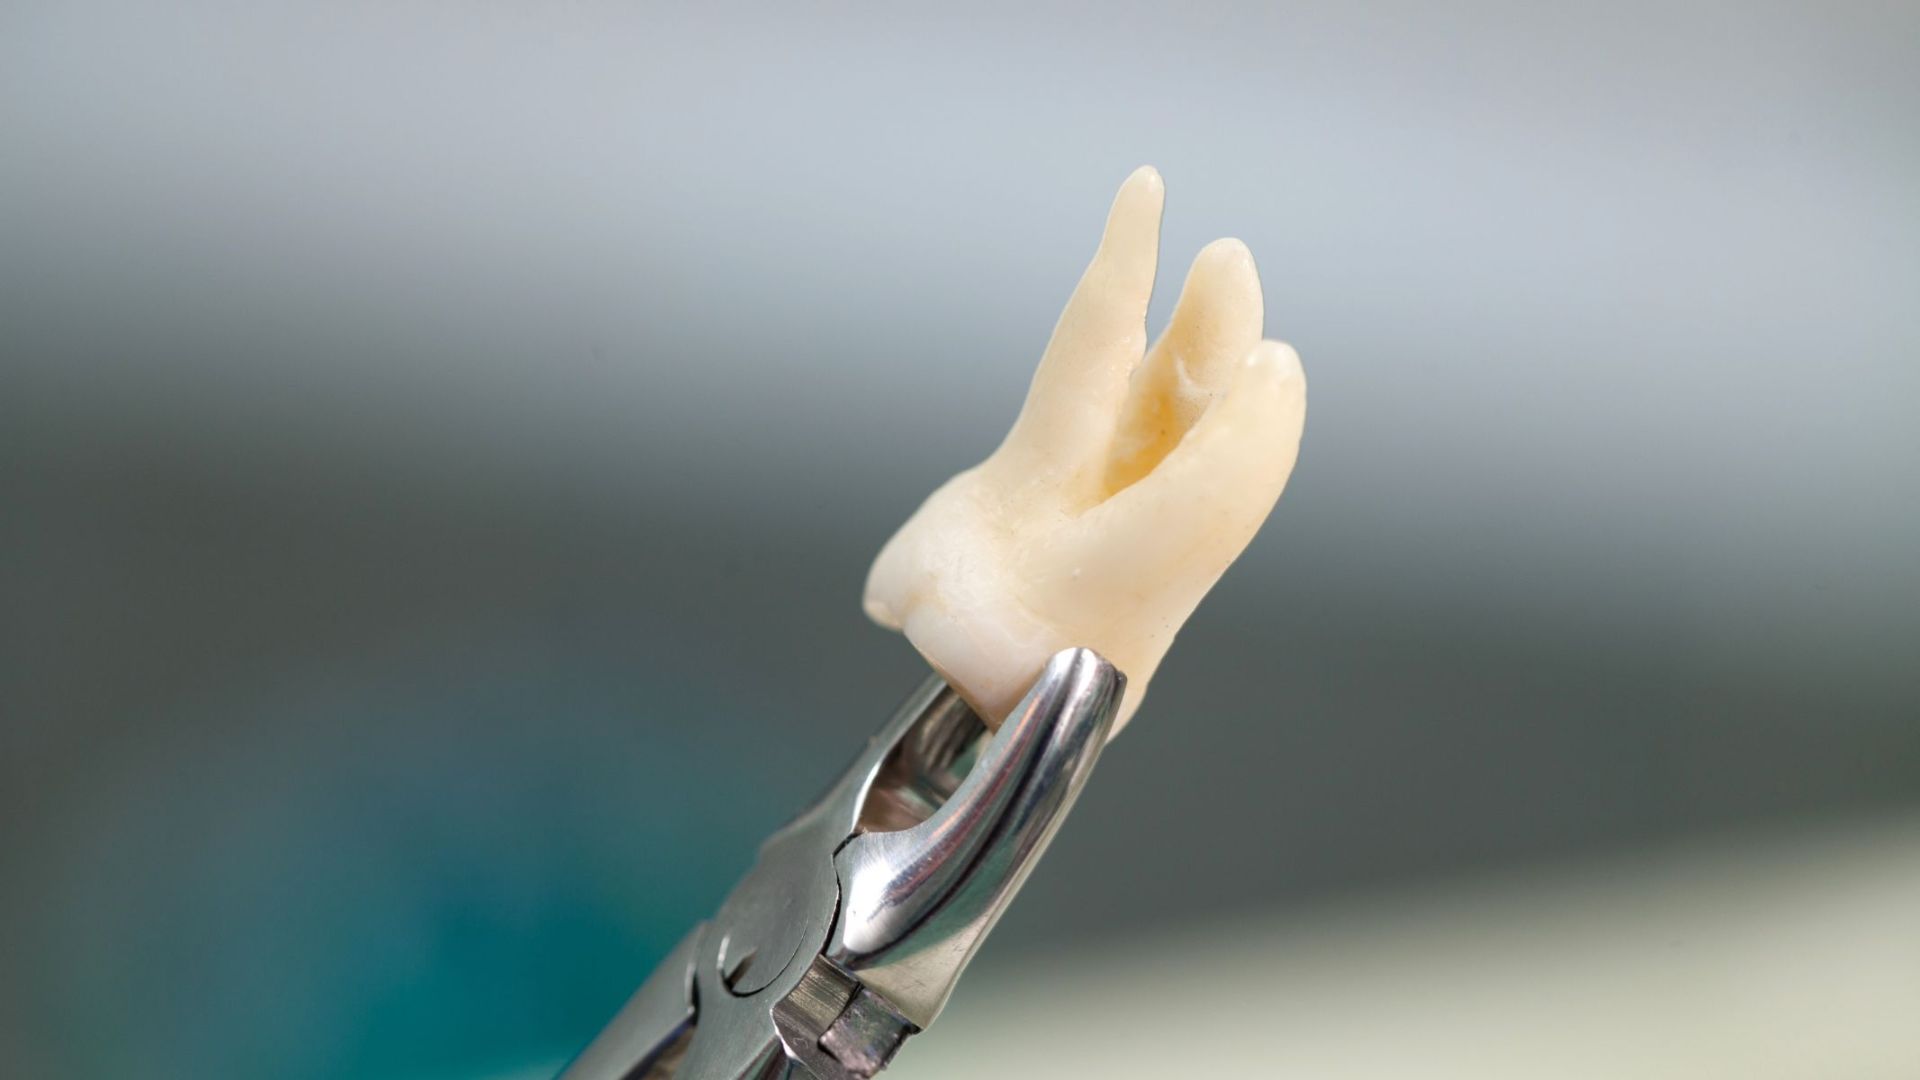

Nhổ răng khôn là tiểu phẫu nha khoa phổ biến, được thực hiện an toàn tại các cơ sở nha khoa. Quy trình thường diễn ra theo các bước sau:

- Thăm khám và chụp phim (X-quang răng hoặc CT Cone Beam) để đánh giá vị trí răng khôn, độ khó, mối quan hệ với dây thần kinh và xoang hàm.

- Gây tê cục bộ (hoặc gây mê nếu cần).

- Bác sĩ rạch nướu (nếu răng ngầm hoặc kẹt), cắt xương nếu cần, chia nhỏ răng và lấy ra từng phần.

- Sau đó khâu vết thương và đặt gạc cầm máu.

Sau nhổ, bạn cần tuân thủ chăm sóc kỹ lưỡng:

- Chườm đá giảm sưng trong 24 - 48 giờ đầu.

- Uống thuốc theo chỉ định (kháng sinh, giảm đau, chống viêm).

- Ăn thức ăn mềm, tránh nhai bên vết nhổ, không hút thuốc hoặc dùng ống hút.

- Vệ sinh miệng nhẹ nhàng, súc nước muối sinh lý từ ngày thứ 2.

- Tái khám đúng hẹn để cắt chỉ và kiểm tra lành thương.

Hầu hết trường hợp hồi phục tốt trong 7 - 14 ngày nếu được chăm sóc đúng cách.